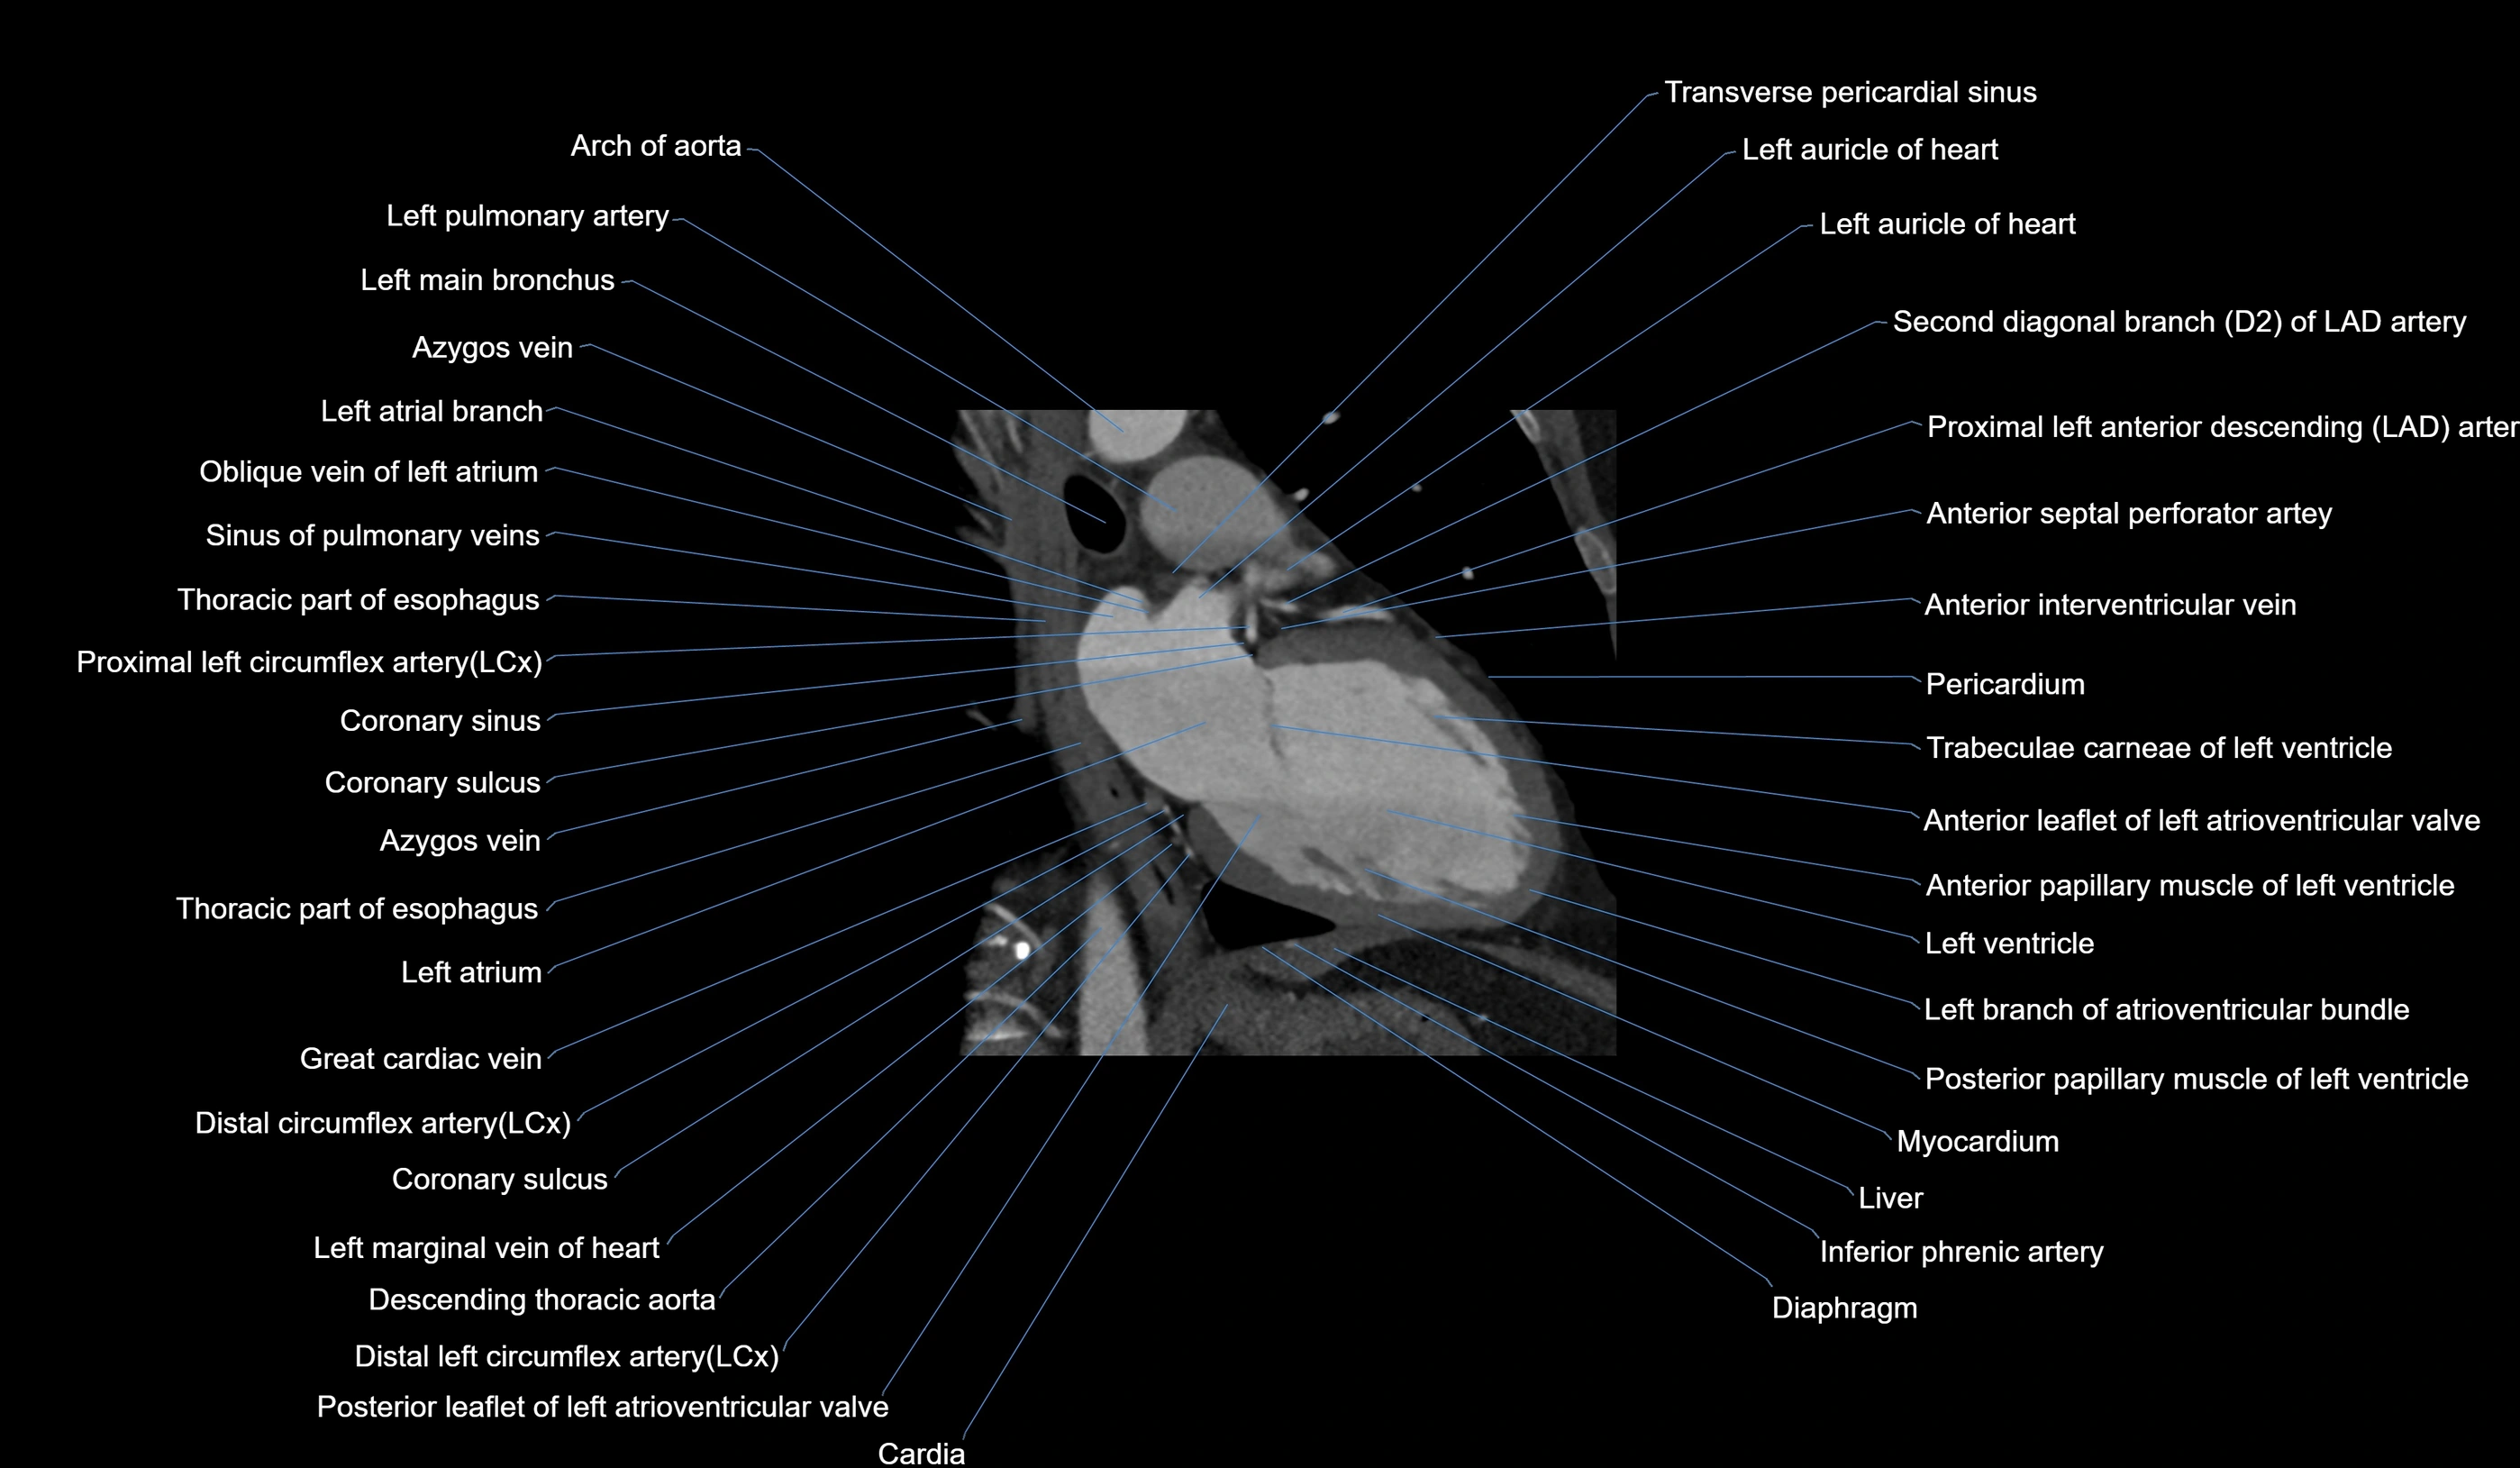

- Acute marginal artery (AM)

The acute marginal artery (AM) is one of the main branches of the right coronary artery (RCA). It typically arises from the mid to distal segment of the RCA and courses along the acute margin (right inferolateral border) of the right ventricle. The AM artery runs within the epicardial fat and supplies blood primarily to the right ventricular free wall.

The number and size of AM branches vary: most individuals have one dominant acute marginal artery, but some may have multiple smaller branches. The vessel is of high clinical importance in right ventricular infarction, since occlusion or disease of the RCA or AM branch can compromise right ventricular contractility and systemic venous return.

CT Appearance

CT Coronary Angiography (CCTA):

-

Best non-invasive modality for acute marginal artery visualization

Shows origin, course along the acute margin, and right ventricular branches

Detects stenosis, occlusion, calcified and non-calcified plaques, aneurysm, or anomalous course

Multiplanar reformats and 3D reconstructions help in pre-PCI and surgical planning

Critical for assessing right ventricular infarction risk in RCA disease

CT images